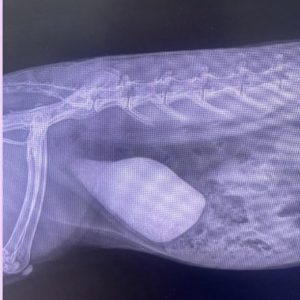

Notice how opaque the bladder is in this x-ray: indicating the accumulation of sediment

Characterised by an excessive amount of calcium deposits in the urine. Which, ultimately accumulates in the bladder as sediment and is difficult to excrete, resulting in pain, secondary infections and can become hard like concrete causing the bladder to be completely

blocked = emergency!